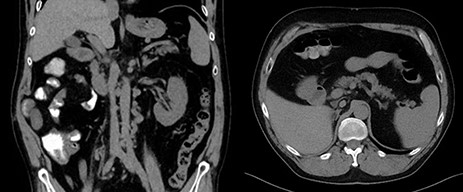

A 58-year-old fit gentleman presented in the mid of 2016 with a large RCC extending into IVC to the liver and multiple lung metastases. It was decided at that time not to do any surgical intervention and to treat solely with Sunitinib. Regular radiological follow-up did show a stable disease, and there was no significant side effects related to Sunitinib. In October 2018, follow-up CT showed complete resolution of lung metastases and extensive thrombus in the IVC extending from iliac bifurcation to the liver, as showed in Fig. 1 [1]. Surgery was done doing radical nephrectomy and complete IVC thrombectomy.

Pre-operative coronal and axial CT images showing right kidney tumor with a large tumor extension into the IVC.